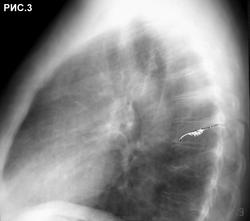

Б-ная 54 г. Живет в небольшом  городе. Поступила в хирургический стационар для холецистэктомии. При ней находился пакет с рентгенограммами органов грудной клетки. Стало известно, что 1 год назад обратилась с бронхолегочными симптомами в поликлинику, где при рентгенографии грудной клетки "выявлено затемнение в легких". После лечения антибиотиками изменения в легких оставались стабильными. Консультирована рентгенологами,онкологами, фтизиатрами, терапевтами, хирургами. Диагноз не установлен. Больная удручена.Хирурги думают. Снимки 6 мес. давности (рис.1,2,3 ).  Рентгенограммы не блеск, но картина везде подобная. Томограмм нет. Ваше слово коллеги! С уважением Nic.

наступил, когда был выполнен последний снимок в отделении. Хорошо видно, что имеется частичное опорожнение ретенционной бронхиальной кисты (рис.4, рис.5). Со слов больной,  незадолго до поступления в стационар имело место отхождение мокроты светлокоричневого цвета без запаха. При анализе выписок из различных учреждений процесс в легких рассматривался как туберкулема легких, туберкулема легких или опухоль, опухоль легкого, патология сосудов легкого, диагноз неясен (овальный фокус затемнения в легком). С уважением Nikolas